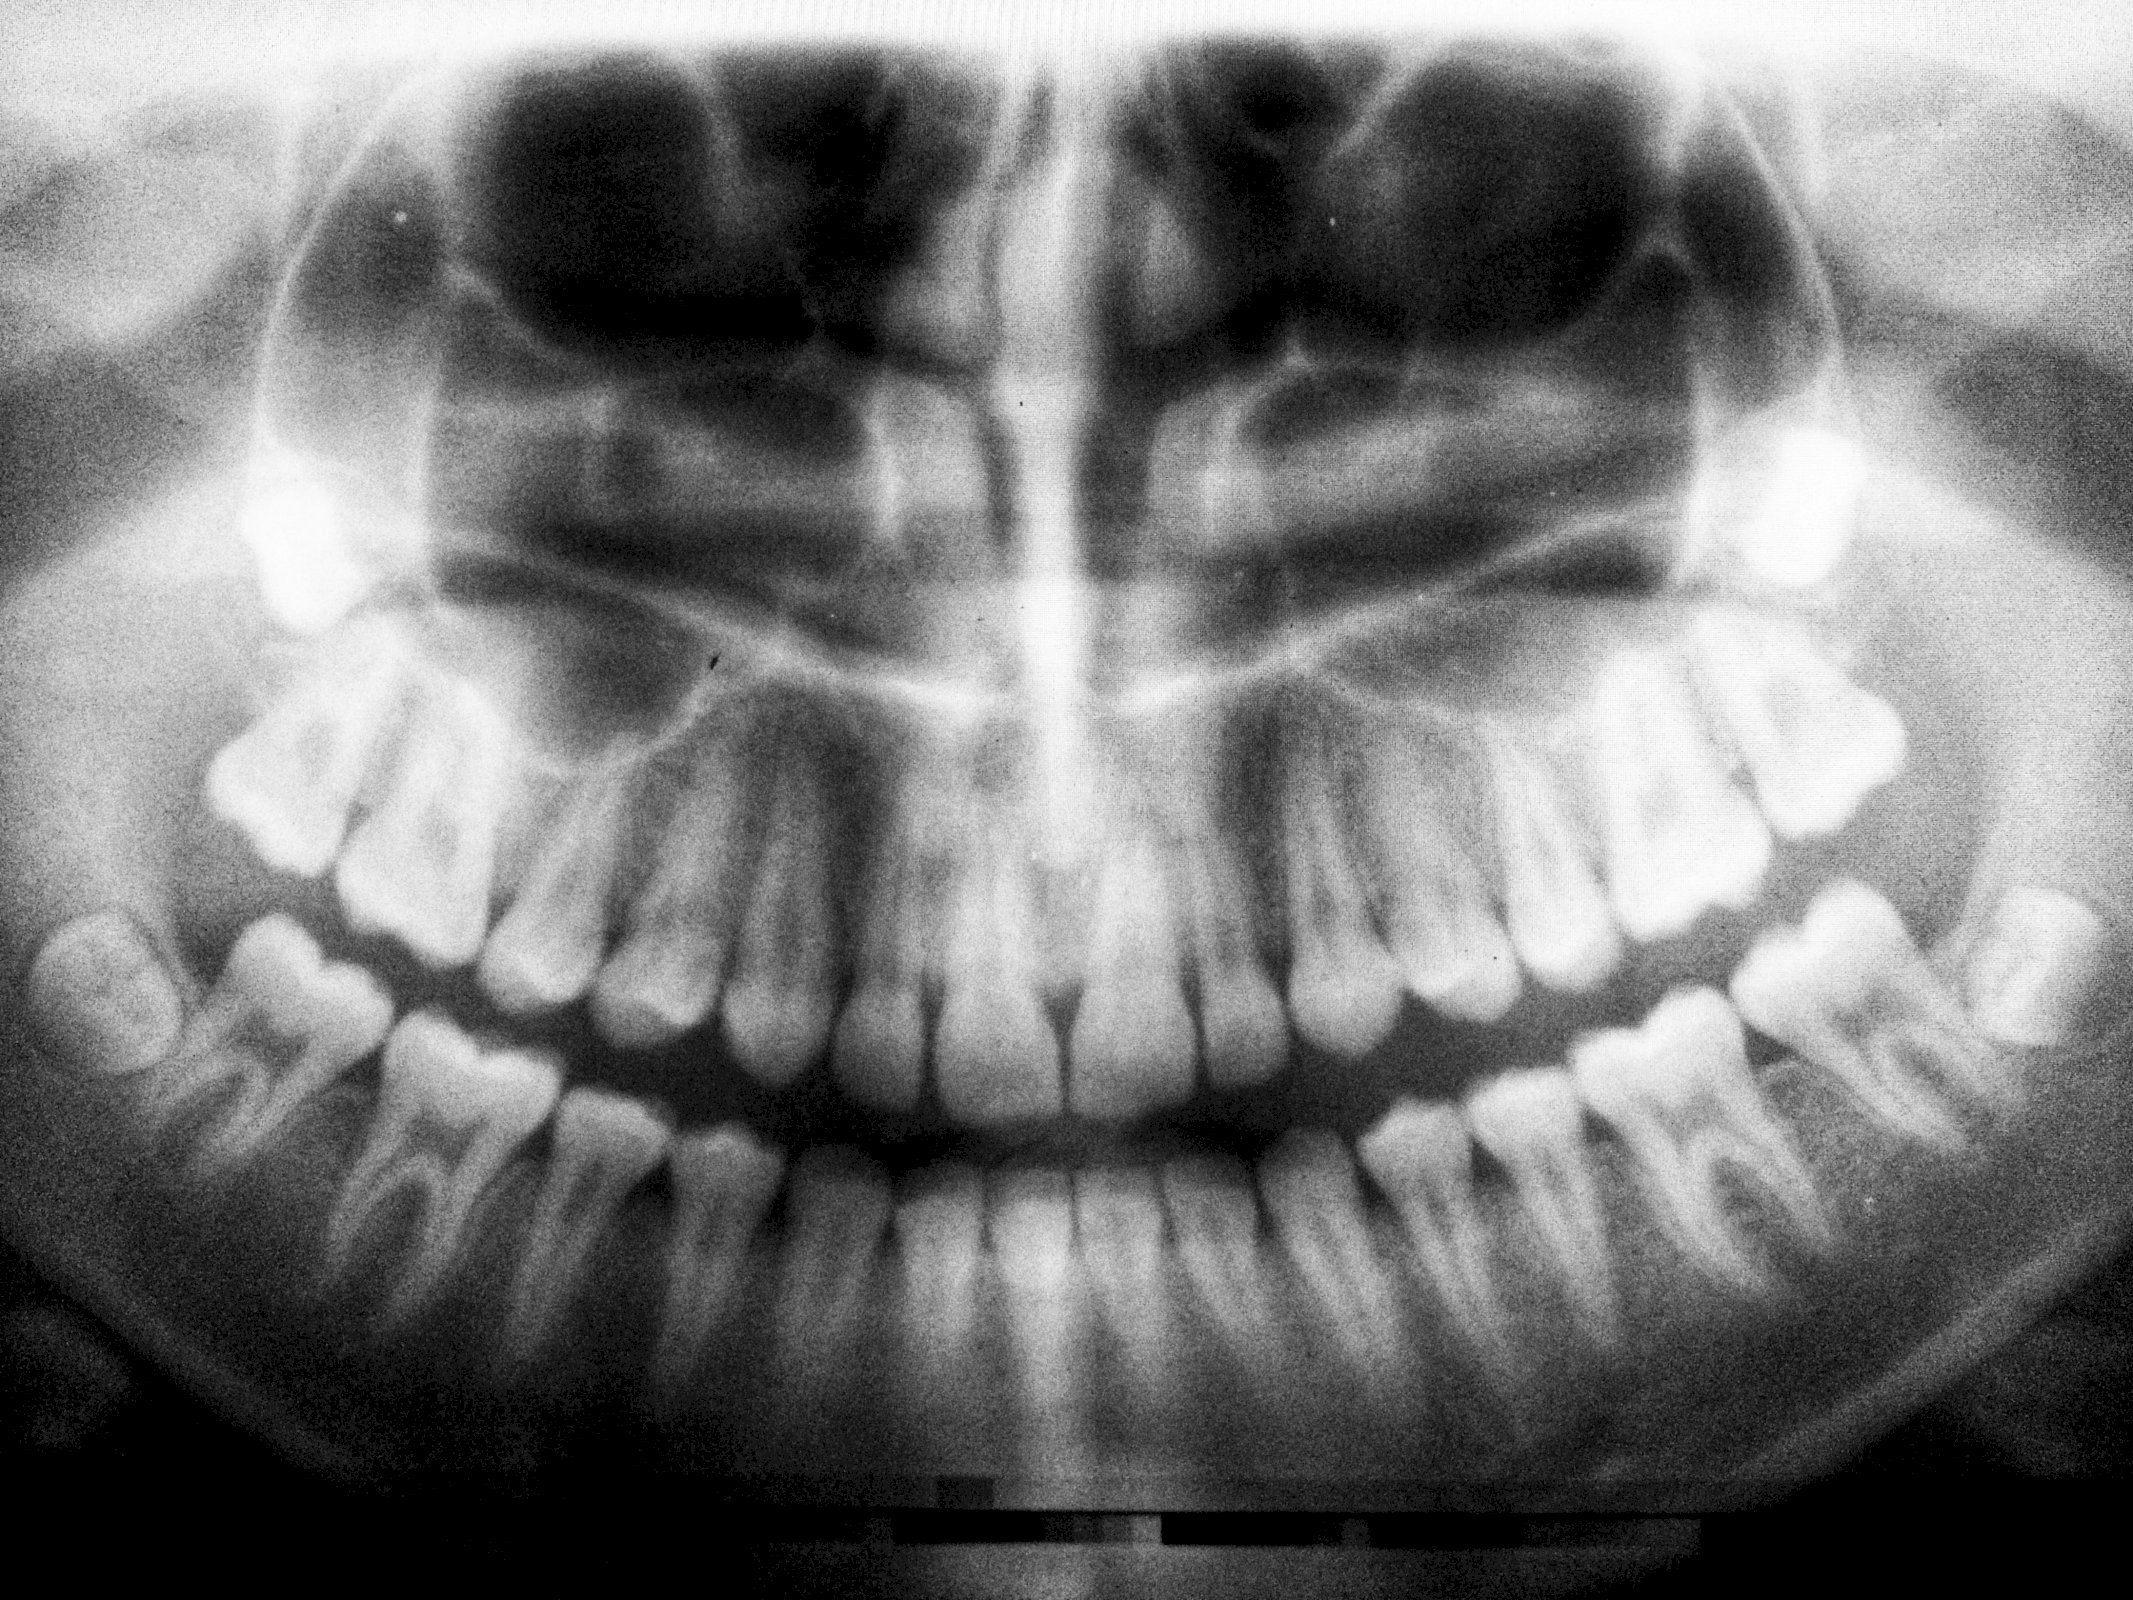

Dentice – soubor zubů v ústní dutině obratlovců. U každé skupiny, popřípadě druhu obratlovců se chrup skládá z pravidelného počtu určitých zubů v horním a dolním oblouku čelistí, které tvoří charakteristický zubní vzorec. Chrup slouží k zachycování a k rozmělňování potravy na sousta nebo k drcení. Vývojově vznikly zuby přeměnou kožních šupin. U ryb, obojživelníků a plazů slouží chrup pouze k uchopení a držení potravy. Skládá se z velkého počtu neustále se obnovujících zubů stejného tvaru – tj. chrup homodontní. Savci mají chrup složený ze zubů různého tvaru, jéž jsou přizpůsobeny různým funkcím – tj. chrup heterodontní. Chrup savců se obnovuje jen jednou v průběhu života. Je rozčleněn na čtyři tvarové a funkční typy: řezáky, dentes incisivi, špičáky, dentes canini, třenovní zuby, dentes premolares, a stoličky, dentes molares. Výjimečně je u savců vyvinut druhotně homodentní chrup, například u delfínů. – Také člověk má v průběhu života dvojí chrup: chrup dočasný (mléčný), který se prořezává od 6 do 24–30 měsíců života dítěte a má 20 zubů; chrup definitivní, který se prořezává od 6. do 14. roku (s výjimkou posledních stoliček, které se prořezávají mezi 18. až 30. rokem života); má 32 zubů.